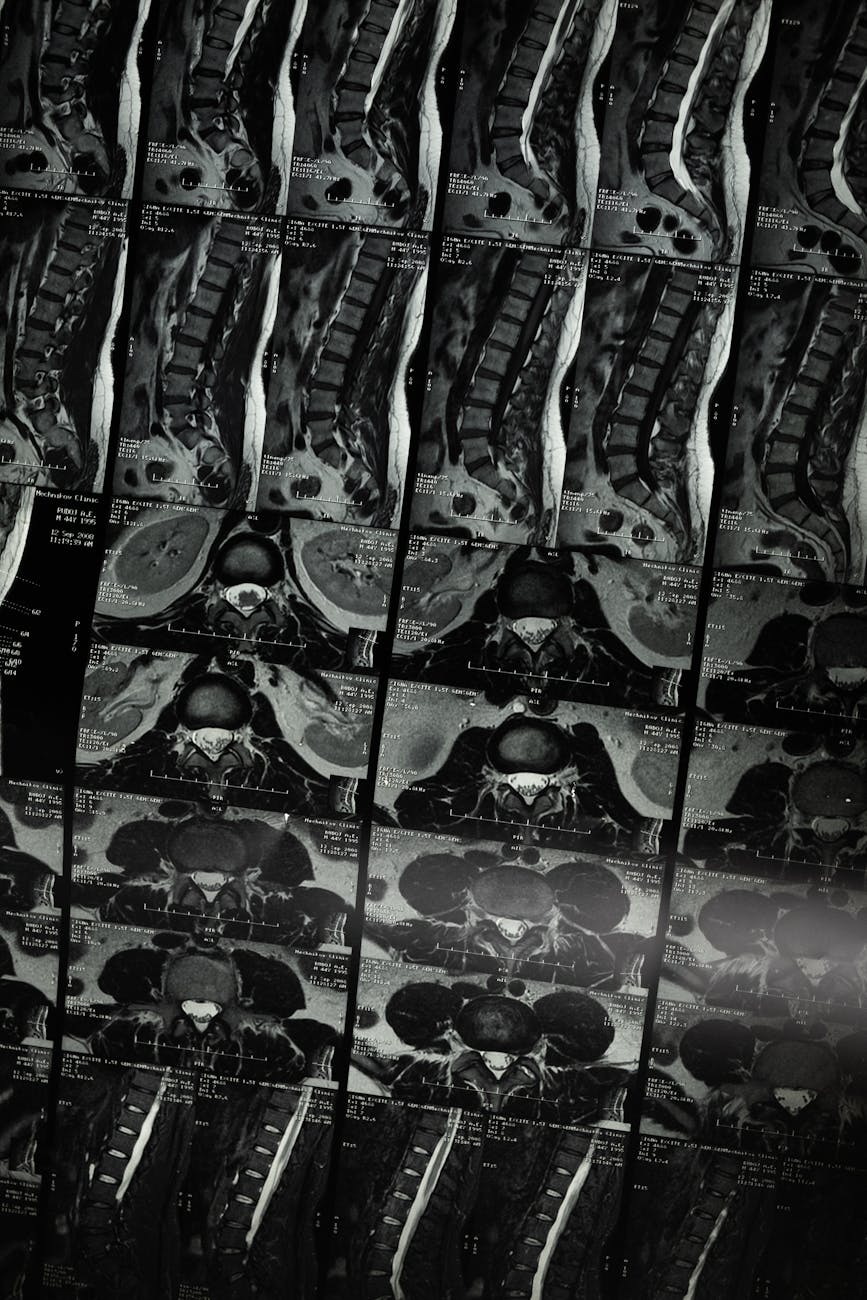

Imaging That Holds Up

We deliver radiology reports that are accurate, defensible, and explain imaging findings for case review.